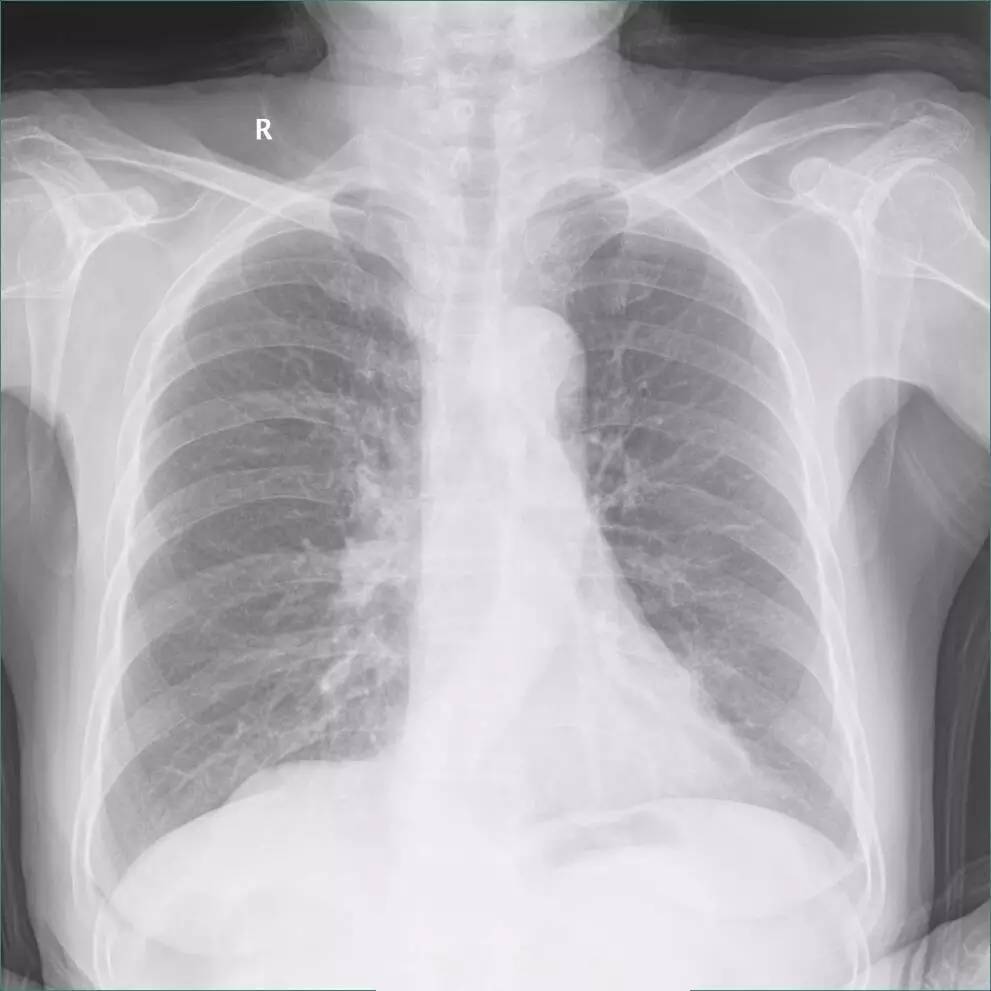

一张二维的胸片中,肋膈角处的异常是胸膜增厚?还是少量胸腔积液,还是模模糊糊分不清?

>>>>病例2:男,88y,右侧胸痛月余。

左下肺最有可能的诊断是?

A.包裹性积液

B.胸膜增厚

C.胸腔积液

D.心包脂肪垫